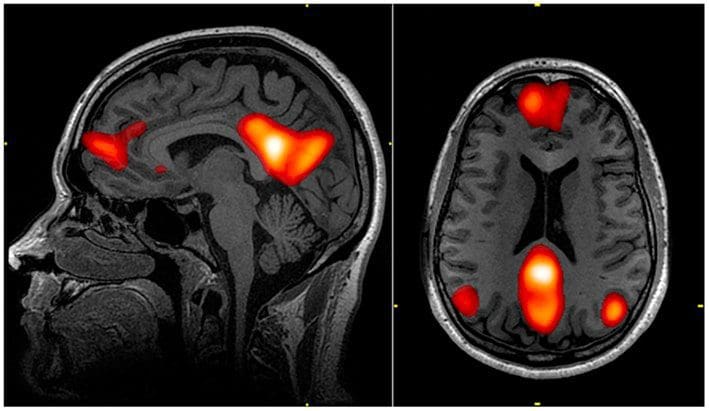

There are 2 parts of the lymphatic system, that of the whole body and the glymphatic system for the brain. The study found that helping clear cellular trash from the brain’s glymphatic system improved memory. This correlates to healing the brain as we age and ties back into one of the benefits of floating. The glymphatic system is more active when we are resting and sleeping so resting in a isolation tank is especially supportive of our brain’s waste removal for some people.

Floating helps with Brain Clearing

Floating in a sensory deprivation tank, or floatation therapy, can help promote lymphatic drainage by creating a weightless environment that improves circulation and allows the body to relax, potentially aiding in the removal of toxins and waste products.